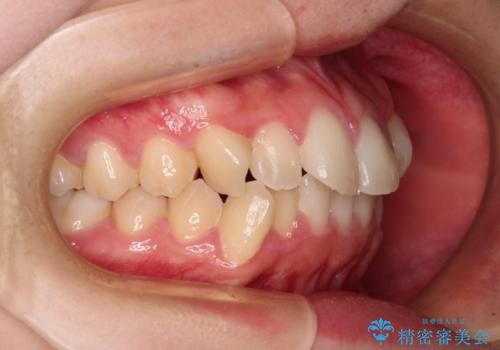

- 口元の閉じにくさを気にして来院された患者様です。

上下ともに歯列が前方に突出していたため、上下左右の第一小臼歯4本を抜去し、ワイヤー装置による矯正治療を行うこととしました。

舌の突出癖による影響もあったため、舌のトレーニングを並行して実施しました。

上下左右4本抜歯する場合には、通常2年から2年半ほどの期間を要しますが、舌のトレーニングをしっかりと行っていただいたことで、1年9ヶ月で終了することができました。